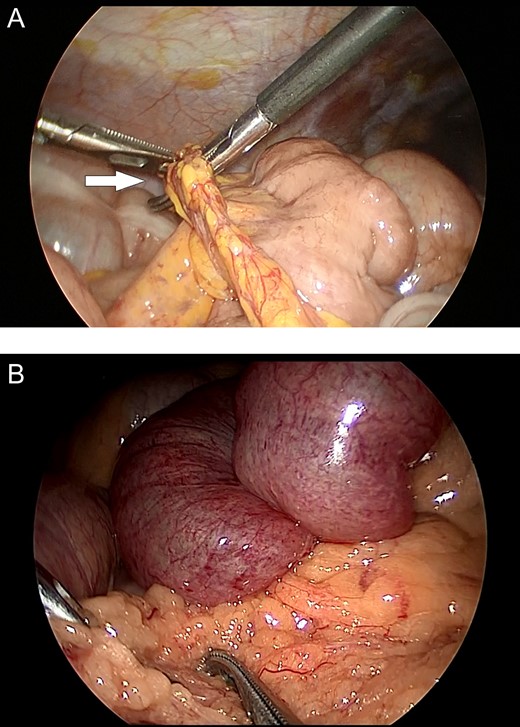

The first patient was a 58-year-old female who presented to our hospital with abdominal pain and vomiting; she had no history of abdominal surgery. Upon performing an examination, her abdomen was soft, with no guarding or rebound tenderness; however, central abdomen palpation revealed tenderness. A laboratory investigation revealed no abnormalities; however, enhanced abdominal computed tomography (CT) revealed intestinal obstruction of the right lower quadrant with the beak sign, indicating the transition zone of SBO (Fig. 1A). Therefore, the patient was diagnosed with strangulation ileus due to the internal hernia. Emergency laparoscopic surgery revealed an incarcerated loop of the small bowel through a greater omental defect (Fig. 2A). The incarcerated small bowel was released; because the ileal segment was viable, bowel resection was deemed unnecessary. The patient was uneventfully discharged on postoperative Day 8.

Intraoperative images. (A) Incarceration of a loop of the small bowel through a defect in the greater omentum (arrow). (B) Small bowel loops appear to be congested and herniate through the greater omentum.

The second patient was a 36-year-old male who presented to our hospital with abdominal pain and had no history of abdominal surgery. His physical examination revealed upper abdominal tenderness. Laboratory investigations revealed no abnormalities except for an abnormal white cell count (11 000 mm3). Enhanced abdominal CT revealed dilated, fluid-filled loops of the small bowel, with caliber change in the upper abdomen (Fig. 1B and C). He was suspected of having transomental hernia, and emergency laparoscopy was performed. During surgery, an ileal segment measuring ~15 cm in length was observed to be herniating through a greater omental defect (Fig. 2B). The small bowel was released by dividing the omentum; there was no evidence of ischemic changes in the incarcerated loop of the small bowel. The postoperative course was uneventful; the patient was discharged on postoperative Day 4.

Recently, laparoscopic surgery has been commonly performed for SBO [6] because of its minimal invasiveness and rapid diagnostic capability. These characteristics make laparoscopic surgery crucial for diagnosing and treating transomental hernia. In particular, the high mobility of the omentum makes detailed observation of transomental hernia possible. When risk factors such as previous abdominal surgery, trauma or peritoneal inflammation are absent in patients presenting with acute abdominal symptoms, the possibility of internal hernia should be considered, and one can expect no adhesions in the peritoneal cavity. Therefore, exploratory laparoscopy is useful for diagnosing SBO in case of SBO with high visibility. If performed early after symptom onset, laparoscopic surgery can completely save an incarcerated small bowel from necrosis. Laparoscopy offers adequate working space, given the high mobility of the omentum.